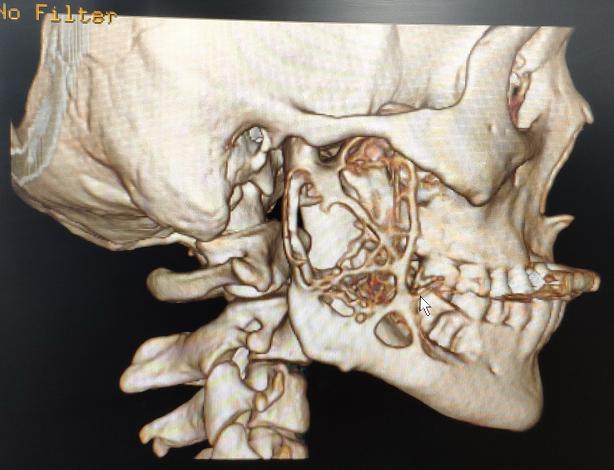

在别人的推荐下,他来到了温医大附一院口腔科就诊。经颌面部三维CT检查,发现在他的右侧下颌骨内部长了一个巨大肿瘤。因肿瘤未在面部皮肤或口内黏膜形成破口,所以未能被及时发现,耽误了及早治疗的契机。

患者下颌骨巨大肿瘤侧面CT三维重建影像